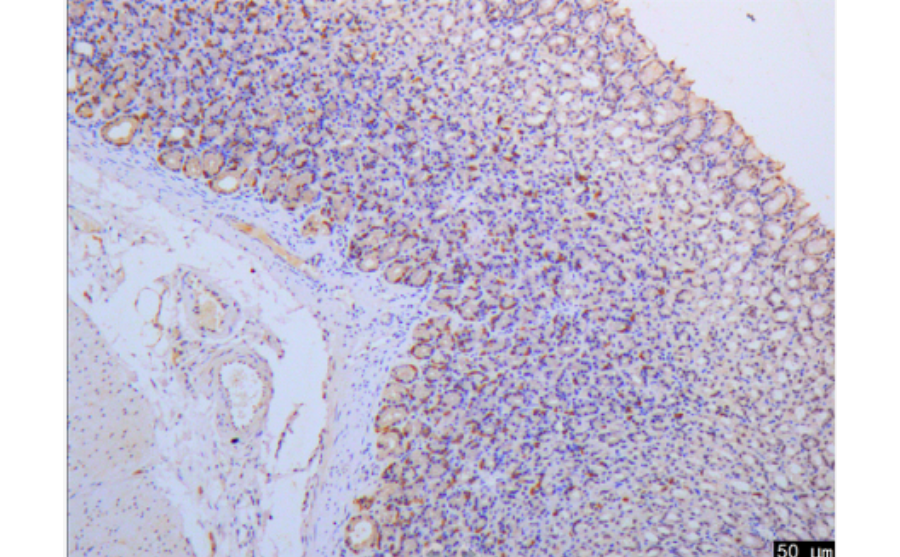

免疫组化,是应用免疫学基本原理——抗原抗体反应,即抗原与抗体特异性结合的原理,通过化学反应使标记抗体的显色剂(荧光素、酶、金属离子、同位素)显色来确定组织细胞内抗原(多肽和蛋白质),对其进行定位、定性及相对定量的研究,称为免疫组织化学技术(immunohistochemistry)或免疫细胞化学技术(immunocytochemistry)

抗体和抗原之间的结合具有高度的特异性,免疫组织化学正是利用了这一原理。先将组织或细胞中的某种化学物质提取出来,以此作为抗原或半抗原,通过免疫动物后获得特异性的抗体,再以此抗体去探测组织或细胞中的同类的抗原物质。由于抗原与抗体的复合物是无色的,因此还必须借助于组织化学的方法将抗原抗体结合的部位显示出来,以其达到对组织或细胞中的未知抗原进行定性,定位或定量的研究。